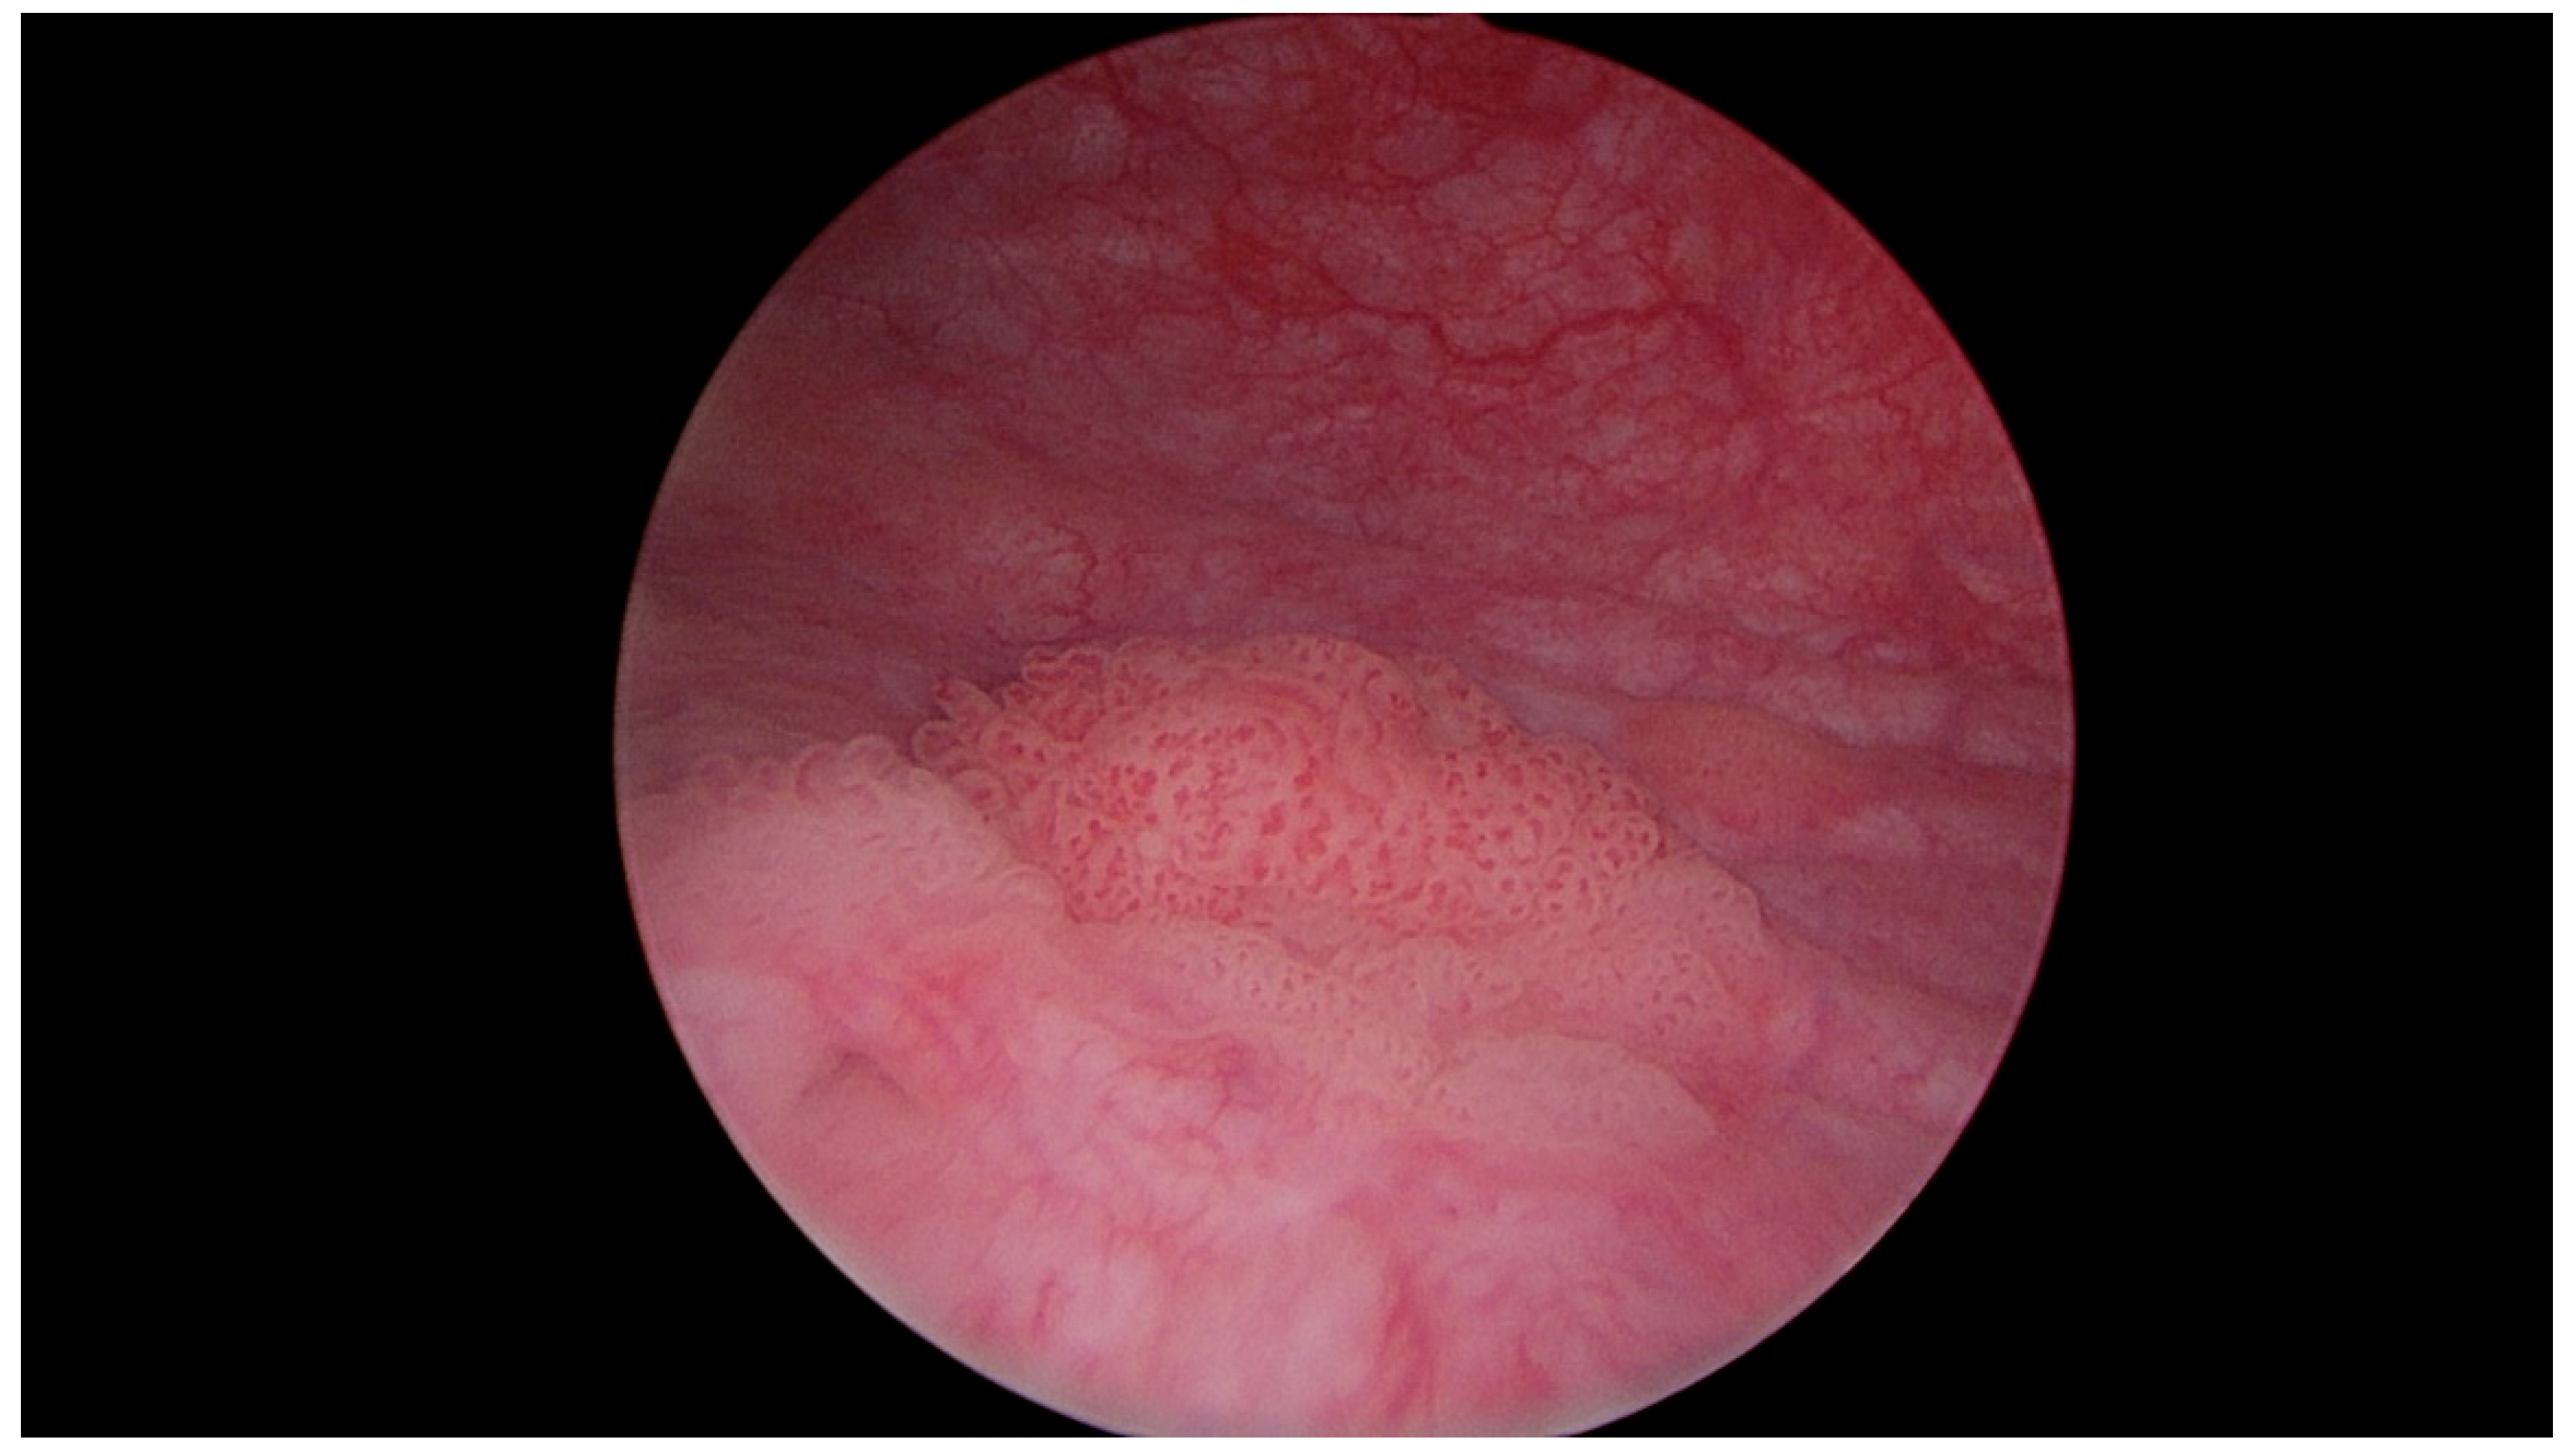

Figure 4.

Papillary urothelial carcinoma of the urinary bladder—visible pathological vascularization within the exophytic part of the tumor, as well as at its base. Own study based on Ethical Approval of the University of Rzeszow, No. 29/05/2019. Titled 12. 2019, Evaluation of the efficacy of the in vitro photodynamic method in superficial bladder cancer, by M.D. Dominik Godlewski.